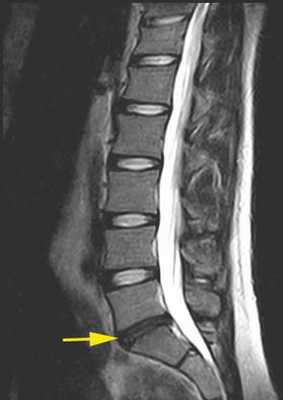

Грыжа шейного отдела на КТ.

Грыжа и клювовидные остеофиты, слева рентген, справа МРТ.